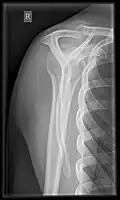

Fracture

Fractures of shoulder bones can include clavicular fractures, scapular fractures, and fractures of the upper humerus.

X-ray

Projectional radiography views of the shoulder include:

- AP-projection 40° posterior oblique after Grashey

The body has to be rotated about 30 to 45 degrees towards the shoulder to be imaged, and the standing or sitting patient lets the arm hang. This method reveals the joint gap and the vertical alignment towards the socket.[26]